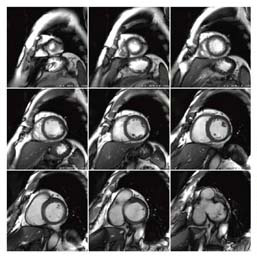

![]() 図6 心臓シネ画像(32chボディアレイコイル) MR Echoによる左室短軸・FIESTA・シネ画像 TR/TE:3.3/1.5,スライス厚 10mm |

奥田:シネMRIも冠動脈MRAも,1.5T MRIではSSFP法による高コントラストを利用して,心臓や血管の内腔を描出することが一般的です。3T MRIにおける心臓検査の最も大きな課題はSSFP法が使いにくいということでした。しかし,Discovery MR750では,SSFP法が問題なく使用できるようになりました。その理由は,4ポイントドライブをはじめとするハードウェアの改良によって安定した画像が得られるようになり,同時にSARの計算がより正確に行えるようになったことが大きいと思います。安全性を担保しながらSARを上限まで使用し,フリップ角を有効に使えるようになったことが,SSFP法にとっては有利に働いているようです。

また,以前は3T MRIでSSFP法を使用するにあたっては,頻繁にシムを取りながら磁場の均一性を確保していかなければならず検査時間が延長すると言われていましたが,Discovery MR750では最初にシムを合わせるだけなので,手間がかかりません。加えてDiscovery MR750では,シネMRI,心筋パーフュージョン,遅延造影MRIまでの一連の流れを1つのユーザーインターフェイスで簡単に行える“MR Echo”という機能があり,操作性の面でも非常に使いやすいので,心臓MRIに慣れていない方でも断面設定などは行いやすいと思います。

2.3T MRIによる検査の実際

奥田:心臓MRIについては現在,3Tで平均週2件の撮像を行っています。左室機能障害,心筋症の評価が多く,シネMRIによる動きの評価と遅延造影MRIによる心筋の性状評価が検査の中心です。遅延造影MRIでは,心筋の線維化の有無や病的な心筋の分布などが画像化できますが,これは他のモダリティでは得られない情報ですので,主治医からの要望が非常に多いです。一方,虚血性心疾患の評価にはシネMRI,パーフュージョンMRI,遅延造影MRIを行います。パーフュージョンMRIについては,3Tではつい先日初めて撮像を行い,良好な画質が得られました。